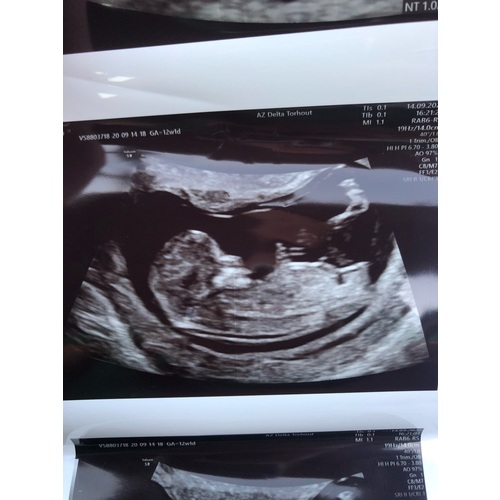

Dit is bij 13 weken, ik dacht zelf een jongen te zien volgens nub. Toen was nog niks tussen de benen te vinden op de echo. Nu bij 15 weken overduidelijk een jongen, dus had het met de nub juist.

Bij ons waren er verschillende antwoorden gegeven, zowel jongen als meisje. Het word een meisje 馃挅 de echo was van 11+5